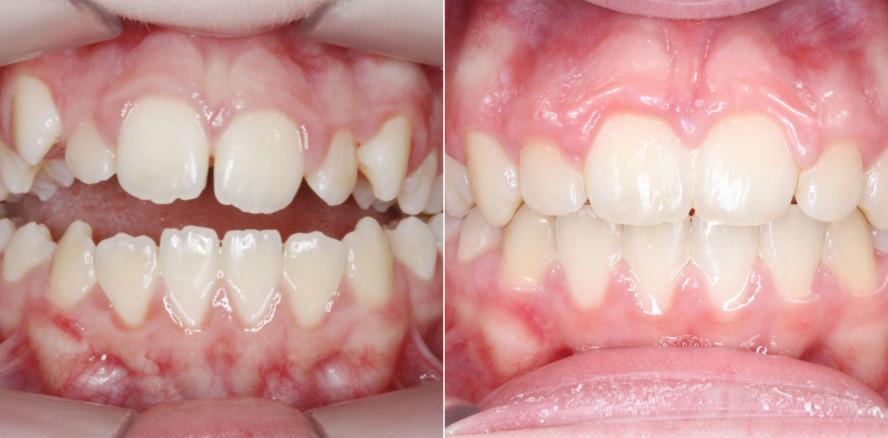

Eine 13-jährige Patientin stellte sich mit beidseitigem Kreuzbiss, einem anterioren offenen Biss und einer Angle Klasse II vor. Das viszerale Schluckmuster wurde mittels logopädischer Maßnahmen umgestellt, der offene Biss persistierte jedoch (Abb. 3a–l).

Nach erfolgreicher Expansion und Molaren­intrusion wurde eine Multibracket-Therapie zur Ausformung und Koordination der Zahnbögen durchgeführt (Abb. 8a–f). Nach Abschluss der aktiven Behandlungsphase wurden die Apparaturen entfernt und festsitzende Retainer im Ober- und Unterkiefer eingesetzt (Abb. 9a–k).